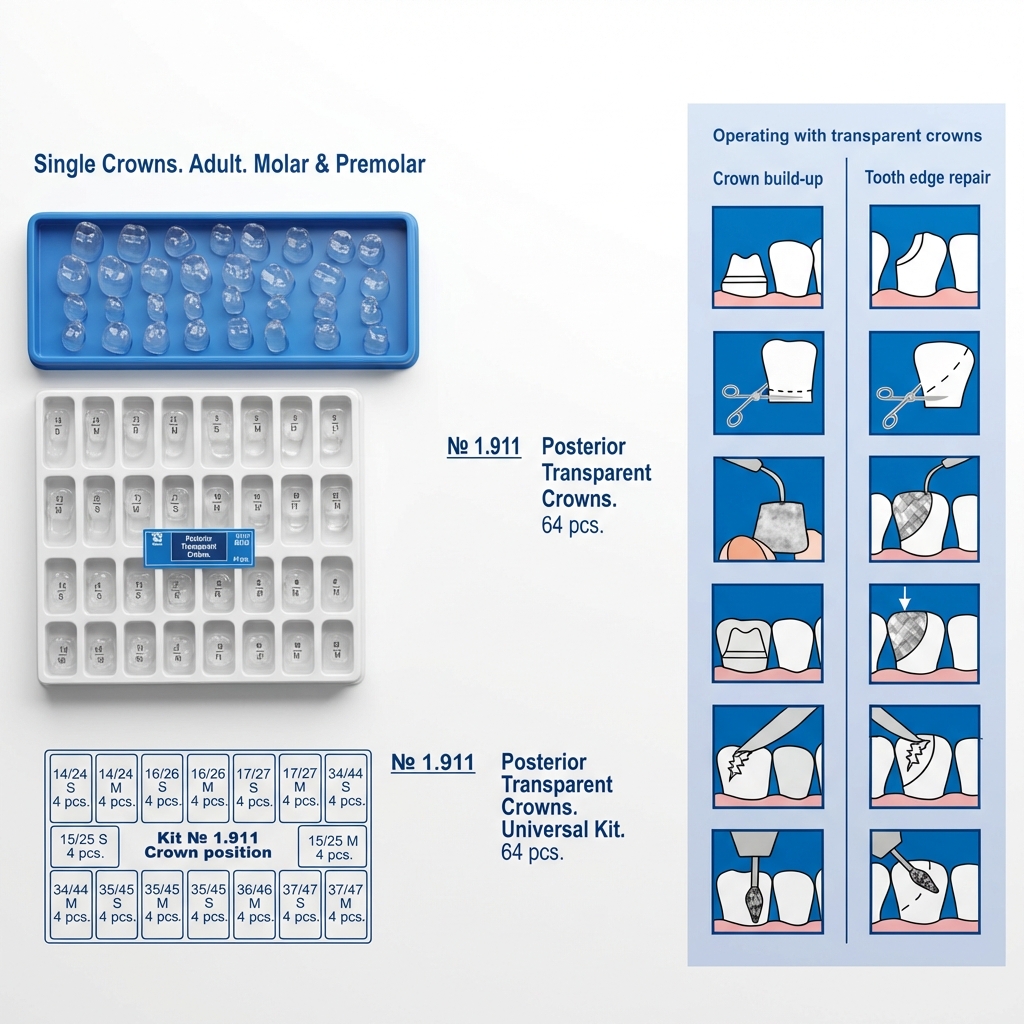

A: Dentalkart offers a wide range of pediatric crowns, including stainless steel primary crowns, stainless steel primary molars, stainless steel permanent molars, polycarbonate crowns, and transparent strip crowns.

A: The choice of pediatric crown depends on various factors such as the tooth's position, size, and condition. Stainless steel crowns are ideal for posterior teeth, while polycarbonate crowns are suitable for anterior teeth. Transparent strip crowns are useful for esthetic concerns.